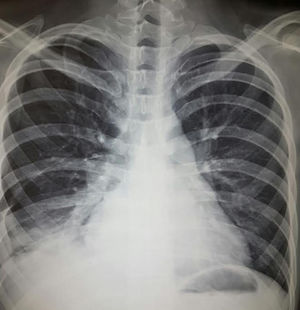

Diagnosis. It can be corroborated by the clinical findings, the unexplained decrease in hemoglobin, the characteristic radiographic findings and the favorable response to treatment. Fig. 4 is a radiograph showing alveolar images characteristic of alveolar hemorrhage. Certain tools that may contribute to the diagnosis include:

A 20-year-old woman with a 4-year history of systemic lupus erythematosus. She had necrotizing vasculitis in lower limbs, psychosis, erythema, photosensitivity, thrombocytopenia, lymphopenia, severe anemia, was positive for Venereal Disease Research Laboratory and had an antinuclear antibody titer of 1:640, homogeneous and peripheral. In recent months, she had developed progressive dyspnea even on minimum exertion; over the last few days, she had increased cough, dyspnea and hemoptysis. Her hemoglobin level was 3g, and she had hypoxemia, nephrotic proteinuria and telescoped sediment. The chest radiograph shows alveolar images compatible with diffuse alveolar hemorrhage. The patient received 1g methylprednisolone for 3 days and cyclophosphamide and the response was satisfactory.